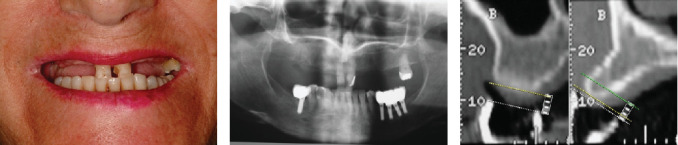

需要上颌种植体康复的部分义齿,无论是使用分段式还是夹板固定义齿,通常都需要进行三维牙位规划。这种规划可能导致牙冠边缘接触或侵蚀剩余的牙槽骨,这是以前的上牙疹的后果。上萌牙与牙周生长有关,牙周韧带和牙周骨与萌牙同时发育。在这种情况下,为了获得成功的结果,在植入假体之前进行骨重塑是至关重要的,为生物宽度创造足够的空间,这对于实现分段、种植体支持、固定的假体是必不可少的。在本病例报告中,患者接受了8个假体和4个固定部分假体,在使用假体18年后,种植体周围炎需要移除后路假体,需要在相应象限重新治疗。值得注意的是,假体之间的近端接触已经打开,可能是由于颅面继续生长和骨重塑,尽管这并不影响患者的功能。修复后的骨和软组织保持原位,近端间乳头和牙龈轮廓均保留在美观区。

Partial edentulism requiring maxillary rehabilitation with dental implants, whether using segmented or splinted fixed prostheses, often involves three-dimensional tooth position planning. This planning can lead to crown margins that either contact or encroach upon the remaining alveolar bone, a consequence of previous supraeruption. Supraeruption is associated with periodontal growth, where the periodontal ligament and bone develop concurrently with the erupting tooth. For successful outcomes in such cases, it is crucial to perform bone recontouring before implant placement, creating adequate space for the biological width, which is essential for achieving a segmented, implant-supported, fixed prosthesis. In the patient described in this case report, who received eight implants and four fixed partial prostheses, peri-implantitis required the removal of a posterior implant after 18 years of prosthesis use, necessitating retreatment in the corresponding quadrant. Notably, interproximal contacts between the prostheses had opened, likely due to continued craniofacial growth and bone remodeling, although this did not affect the patient's functionality. The recontoured bone and soft tissues maintained their position, preserving both the interproximal papillae and gingival contour in the esthetic zone.